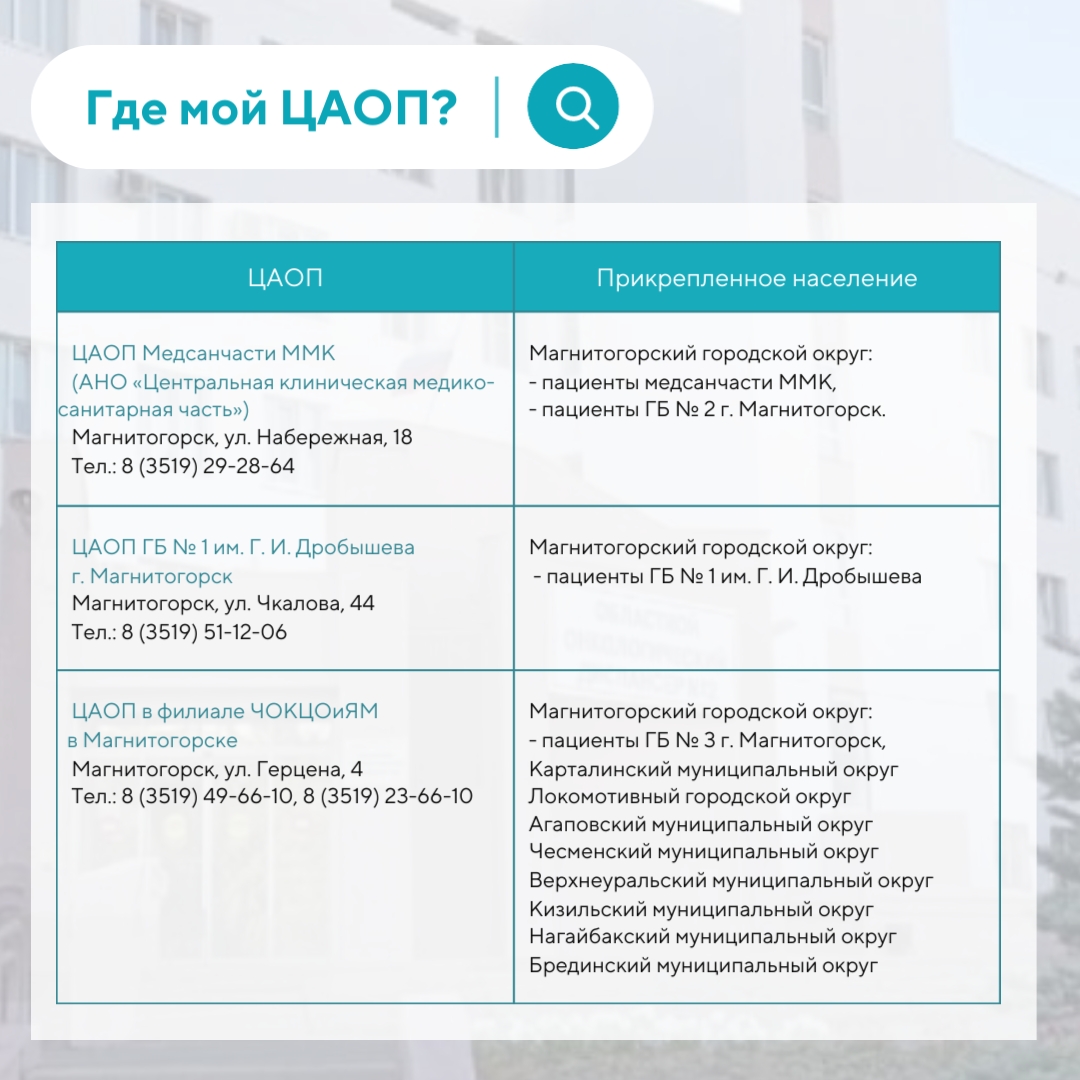

В Челябинской области пациенты прикреплены к конкретным Центрам амбулаторной онкологической помощи, а найти свой можно в карточках:

В Челябинской области пациенты прикреплены к конкретным Центрам амбулаторной онкологической помощи, а найти свой можно в карточках:

Инфографика предоставлена пресс-службой ЧОКЦОиЯМ

Инфографика предоставлена пресс-службой ЧОКЦОиЯМ

Инфографика предоставлена пресс-службой ЧОКЦОиЯМ

Инфографика предоставлена пресс-службой ЧОКЦОиЯМ

Инфографика предоставлена пресс-службой ЧОКЦОиЯМ